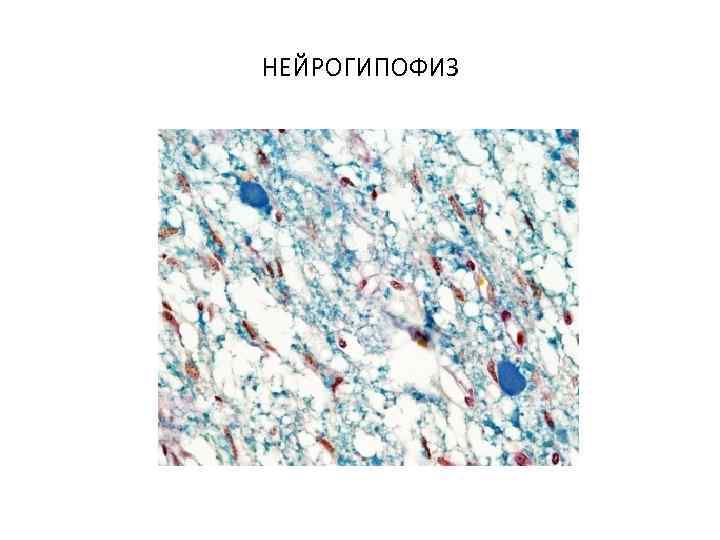

НЕЙРОГИПОФИЗ

НЕЙРОГИПОФИЗ

ГОРМОНЫ НЕЙРОГИПОФИЗА 1. АДГ (антидиуретический гормон, вазопрессин) • Снижение объема мочи 2. Окситоцин • Сокращение матки Оба гормона суживают мелкие кровеносные сосуды и повышают давление.

ГОРМОНЫ НЕЙРОГИПОФИЗА 1. АДГ (антидиуретический гормон, вазопрессин) • Снижение объема мочи 2. Окситоцин • Сокращение матки Оба гормона суживают мелкие кровеносные сосуды и повышают давление.